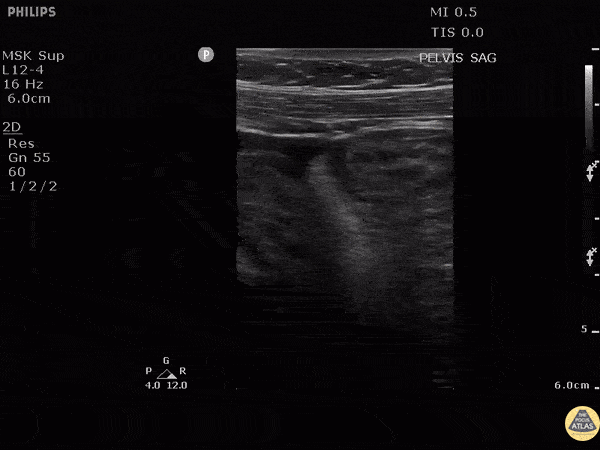

Bowel-GI - Mesenteric Vasculitis

Patient has a history of SLE with abdominal pain and distention. POCUS shows abdominal free fluid and bowel wall thickening. Ultimately after CT and further testing confirmed this as SLE-induced mesenteric vasculitis. Image courtesy of Robert Jones DO, FACEP @RJonesSonoEM Director, Emergency Ultrasound; MetroHealth Medical Center; Professor, Case Western Reserve Medical School, Cleveland, OH View his original post here